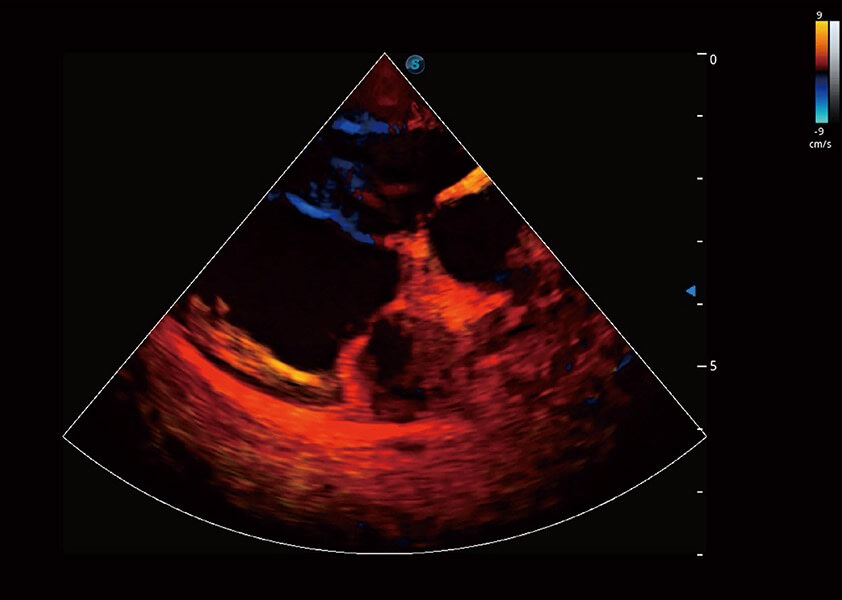

(犬)心脏组织多普勒

• TDI 组织多普勒成像

实时用颜色表示心肌组织运动,观察和定量组织的运动情况,对快速检测与评估心肌的灌注和活性、电传导及心肌收缩和舒张功能等均能提供重要的诊断信息。